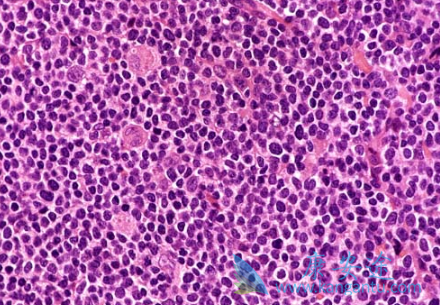

三项研究展示了酪氨酸激酶(BTK)抑制剂依鲁替尼(IBRUTINIB)在治疗复发/难治性套细胞淋巴瘤(MCL)和淋巴细胞性白血病(CLL)的进展。依鲁替尼单药对MCL的治疗:此项研究是基于370位MCL患者治疗的汇总分析以及3.5年的后续随访得出的,主要是用依鲁替尼治疗,作为三项开放期研究的一部分,其后续随访在三项研究中交叉进行,包括额外的暴露治疗。

该项研究对患者使用依鲁替尼的时间和方式以及暴露时间有具体的要求。在41个月的随访后,患者完全缓解率是26.5%,中位生存期是26.7个月。患者2年总生存率为53%,3年总生存率为45%, 5年总生存率为37% (95%CI, 0.25-0.49)。第一年后新的发病事件减少,最常见的3级以上的TEAEs包括嗜中性白血球减少症(17.0%)、血小板减少症(12.2%)、肺炎(11.9%)、贫血(9.5%)、心房颤动(5.9%)和高血压(5.1%)。

多数出现在依鲁替尼(IBRUTINIB)治疗的一年内。治疗紧急的严重不良事件(SAEs)有229例(61.9%),随时间延长初发病的SAEs降低。此次研究的观察数据是从年老、初患CLL的CLL病人的三期临床研究中得到的。在与苯丁酸氮芥治疗相比的18.4个月中,依鲁替尼单药在患者群体中减少疾病恶化或死亡率达到84%。